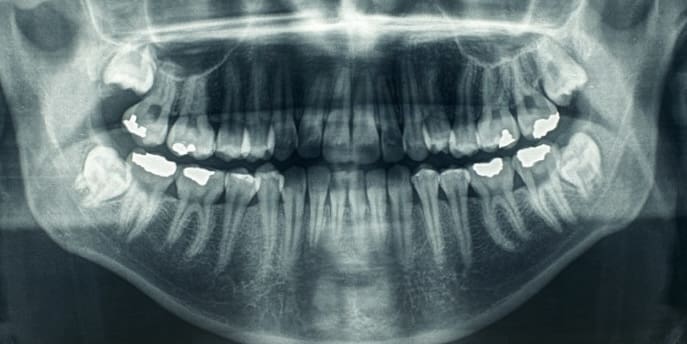

At Origin Dental Wellness, we believe that infected teeth can be a drain on the immune system, potentially leading to deleterious overall health outcomes. Because of this, when a patient has made the difficult decision to have an infected tooth removed, our focus turns to how to replace the missing tooth in the most healthy … Read more